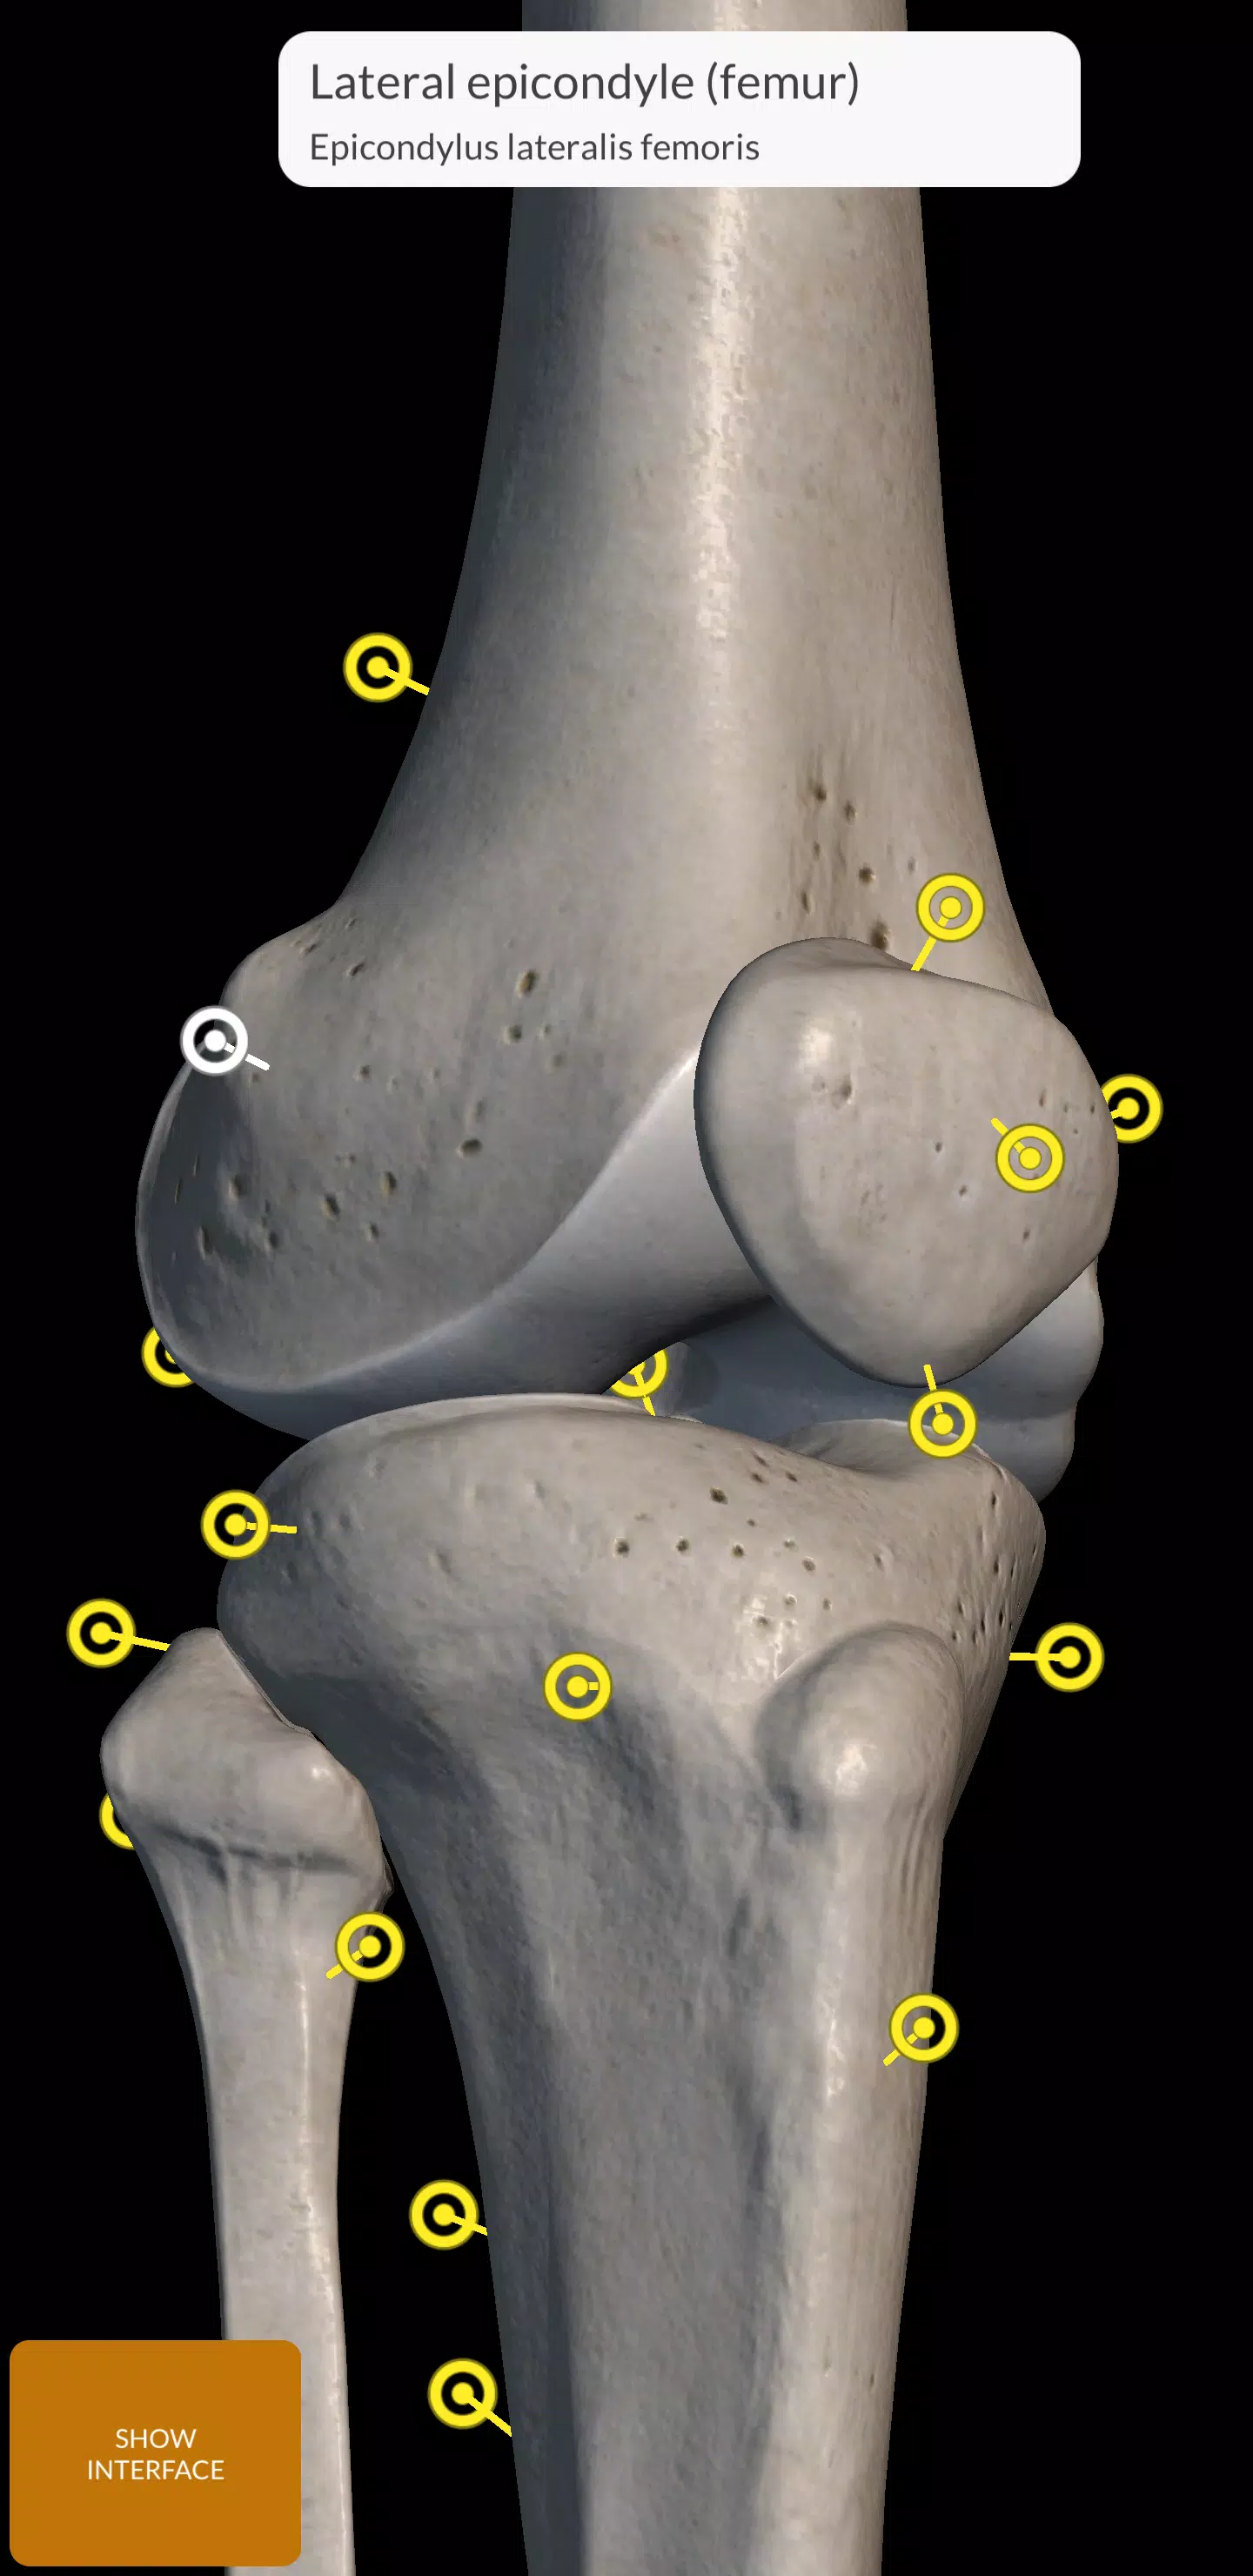

Każda kość w ludzkim szkielecie została skrupulatnie zrekonstruowana w 3D, co pozwala obracać i powiększać każdy model, aby obserwować skomplikowane szczegóły pod dowolnym kątem. Ten poziom szczegółowości jest idealny zarówno do użytku edukacyjnego, jak i profesjonalnego, oferując kompleksowy obraz struktury szkieletowej.

- Zmień i powiększ: Pełna kontrola, aby nawigować w każdym modelu w przestrzeni 3D.

- Podział według regionów: jasna i natychmiastowa wizualizacja każdej struktury anatomicznej.

- Ukryj/pokaż kości: Dostosuj swój widok, ukrywając lub pokazując poszczególne kości.

- Inteligentna rotacja: automatycznie dostosuje się do centrum rotacji w celu łatwiejszej nawigacji.